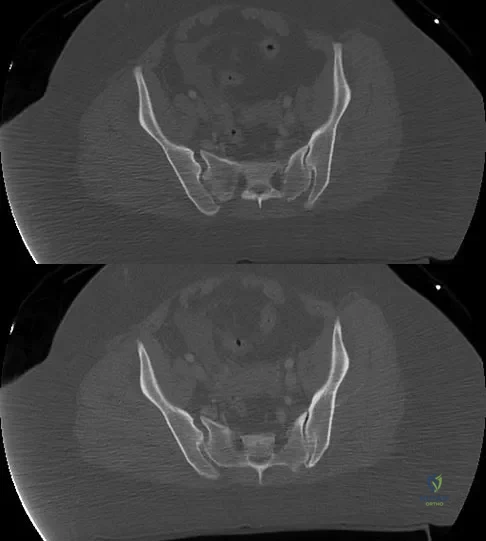

A 36-year-old woman was injured in a train derailment. She has a significant open depressed skull fracture with active bleeding, a hemopneumothorax, and blood in the left upper quadrant and colic gutter by Focused Assessment with Sonography for Trauma (FAST) examination. Additionally, she has the pelvic injury seen on the CT scans in Figures 18a and 18b. The mortality rate for this patient approaches

Detailed Explanation